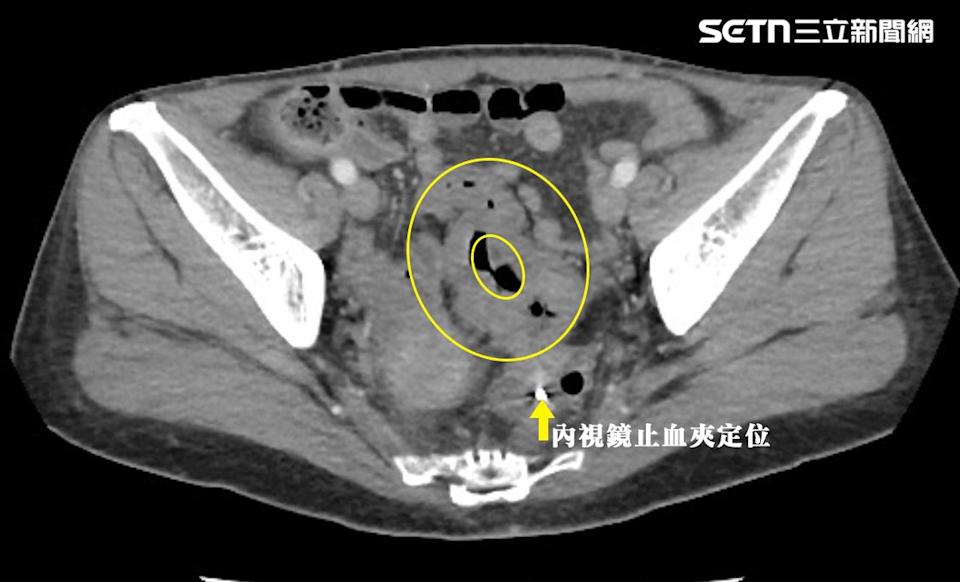

50岁OL因血便长达6个月,确诊直肠癌第三期。(图/翻摄画面)

陈周诚表示,除了饮食习惯有误区,还有许多民众以为血便只是痔疮,之前一名50岁OL因血便长达6个月来就诊,一检查赫见环状大肠恶性肿瘤,经切除化验确诊直肠癌第三期。